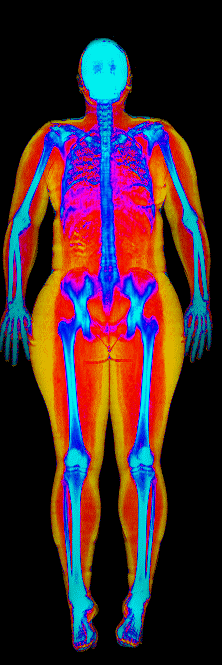

What Muscle Gain Looks Like on a DEXA Scan

Gained 12.0 lb lean, lost 24.9 lb fat · 183 → 170 lb · Age 37

Gained 10.0 lb lean · 140 → 152 lb · Age 23